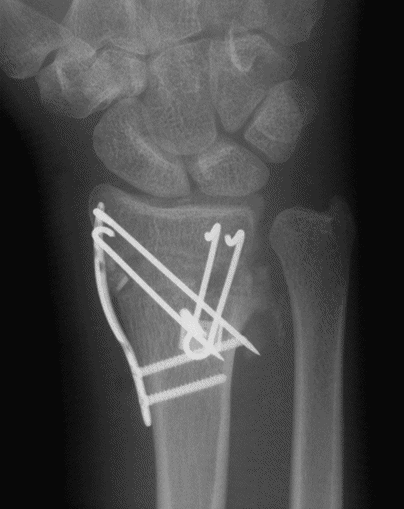

Case 1 Postop